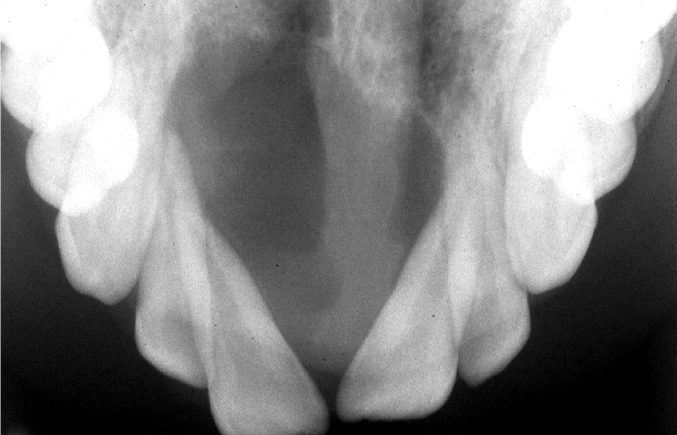

central giant cell granuloma maxillary occlusal radiograph

demonstrates CGCG as cause of divergence of roots of maxillary central incisors